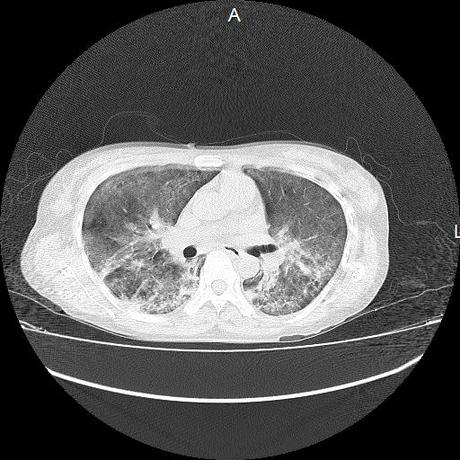

El parénquima pulmonar con areas parcheadas difusas en vidrio despulido combinadas con otras areas hipodensas de baja atenuación debidas a atrapamiento aéreo y engrosamiento intersticial y zonas de fibrosis de predominio en lóbulos medios e inferiores de ambos pulmones.

- LOS HALLAZGOS PUEDEN ESTAR EN RELACIÓN A NEUMOPATIA INTERSTICIAL PROBABLE ETIOLOGIA HIPERSENSITIVA VS AUTOINMUNE/BACTERIANA/FUNGICA.